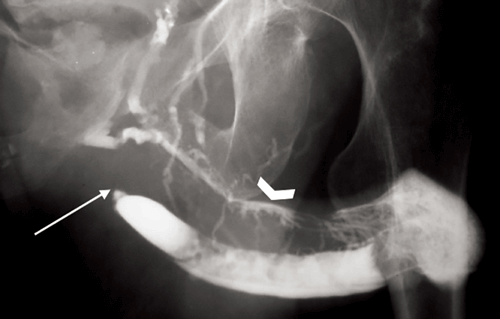

The positioning of the patient is important. Ensure the patient is positioned obliquely so that the whole urethra is elongated and therefore a good view of the length of the urethra is visible. Figures 3 and 4 demonstrate the difference this makes. Figure 5 demonstrates why good filling of the urethra with contrast is important, as strictures may be overcalled secondary to suboptimal filling of the urethra.

Figure 3: Ascending urethrogram demonstrating an irregular, lobulated appearance in the bulbous urethra.

However, the whole urethra cannot be clearly seen as the urethra is not fully oblique.

Figure 4: The patient has been turned more oblique to elongate the urethra so that

the whole length can be clearly visualised. However the urethra is underfilled.

Figure 5: Oblique urethrogram demonstrating a urethral stricture (arrow) and contrast intravasation

into vessels (chevron) due to continued injection of contrast in the presence of the stricture.